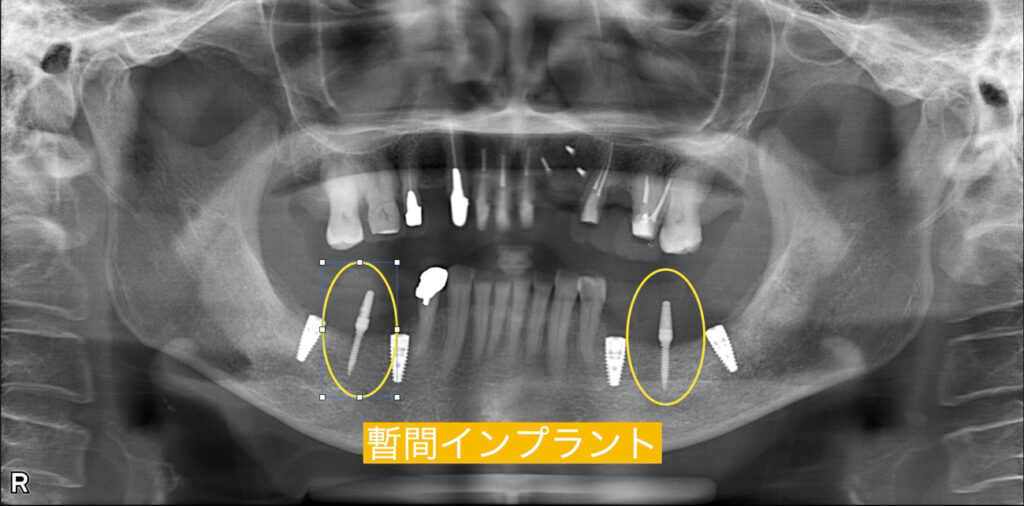

治療中は入れ歯をしたくない

→ 暫間インプラントを使用すればできます!

最終的なインプラントを入れると同時に仮の暫間インプラントを埋入しそこで仮歯を支えます。そうすれば、インプラントに負荷をかけずに治療中も入れ歯を使用することなく患者様はお食事をすることができます。 最終的なインプラントが生着すればそこへ負担をバトンリレーのように移行させれば暫間インプラントは抜きます。

治療後のレントゲン写真

治療後は奥歯にインプラントがしっかりと入り、インプラントの周りは歯茎の移植のFGG(遊離歯肉移植術)を行い清掃性をあげて長持ちの環境も整えております。